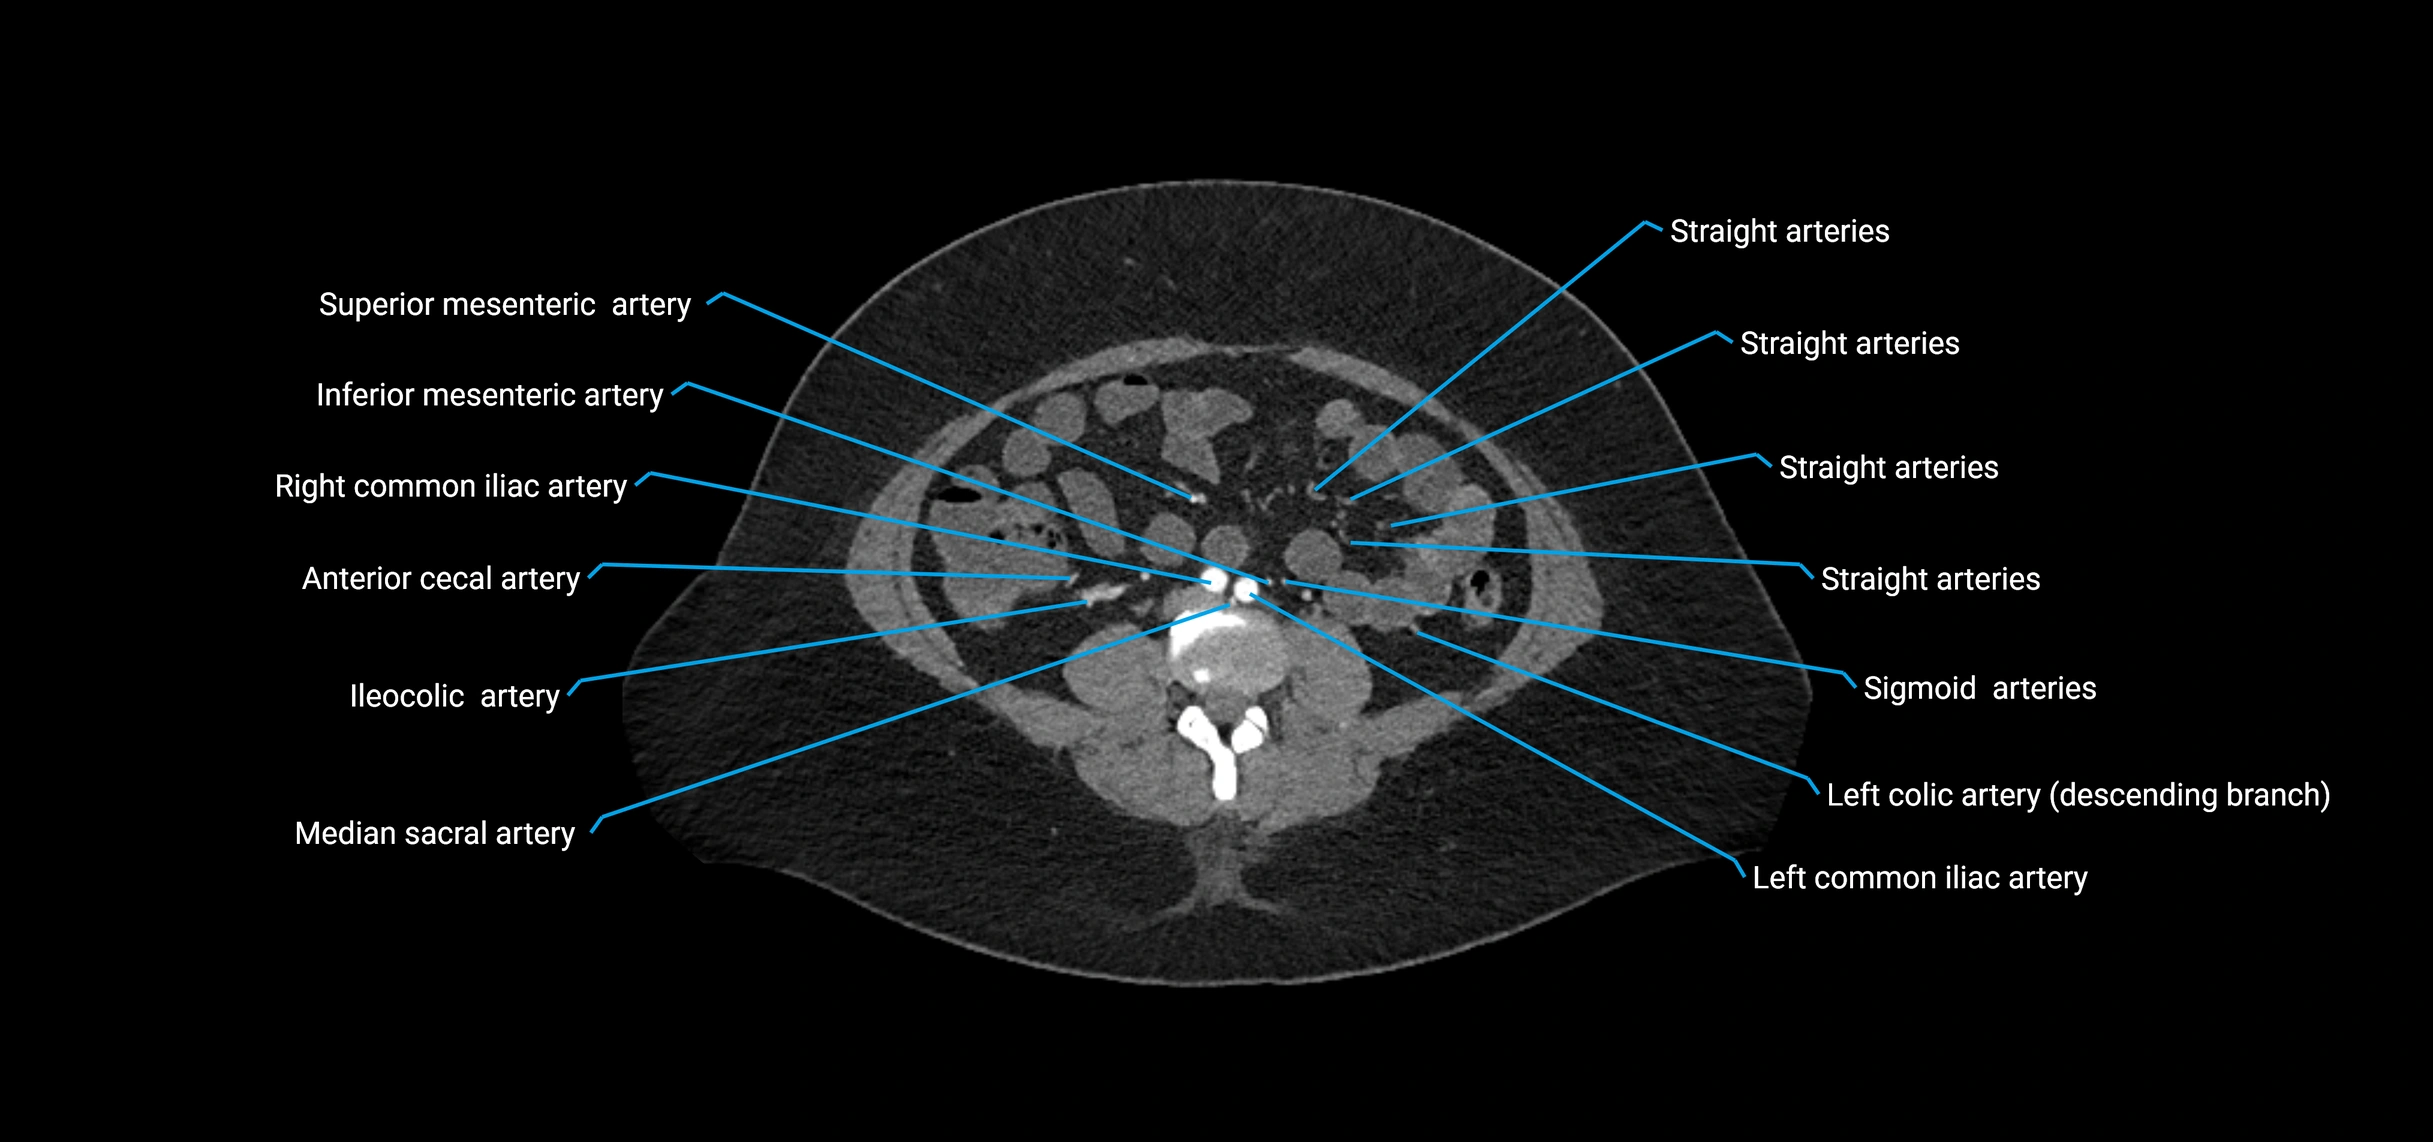

CT images

image